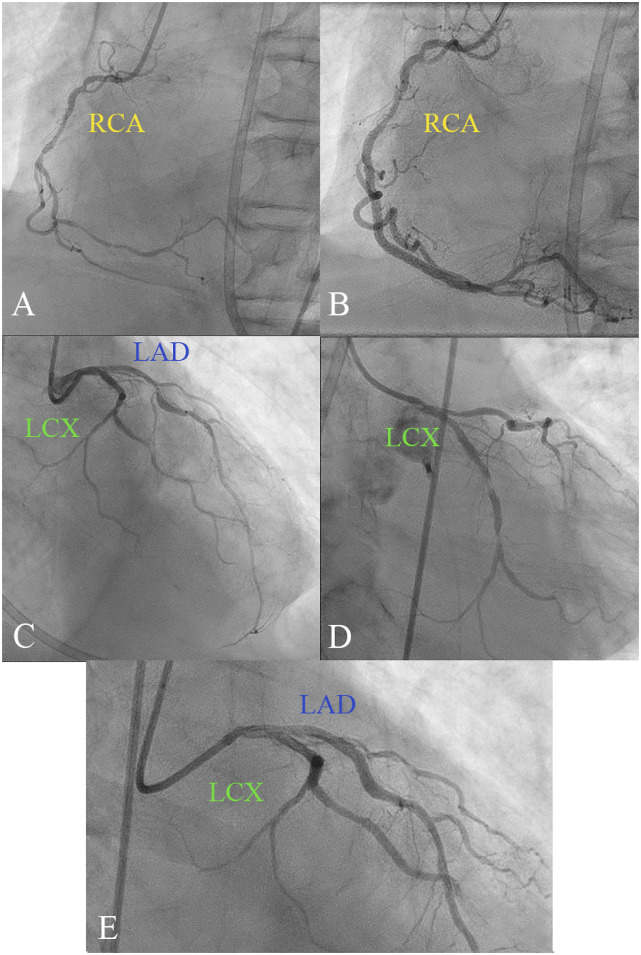

This case challenges the conventional preference for coronary artery bypass grafting (CABG) over percutaneous coronary intervention (PCI) in patients with diabetes, left main coronary artery disease (LMCAD) and multivessel disease. Current guidelines generally recommend CABG, especially in the context of LMCAD. However, our case involves a male patient with diabetes with LMCAD and extensive multivessel disease who was successfully treated with PCI, demonstrating a favorable outcome. Despite the high-risk profile, including a SYNTAX score of 28, the PCI approach was selected. This decision was supported by evidence suggesting comparable outcomes between PCI and CABG in similar patients. Our case highlights the potential of PCI as not just a viable, but potentially superior alternative in specific high-risk patients with diabetes, contrary to the prevailing belief in favor of CABG for all patients with left main involvement.